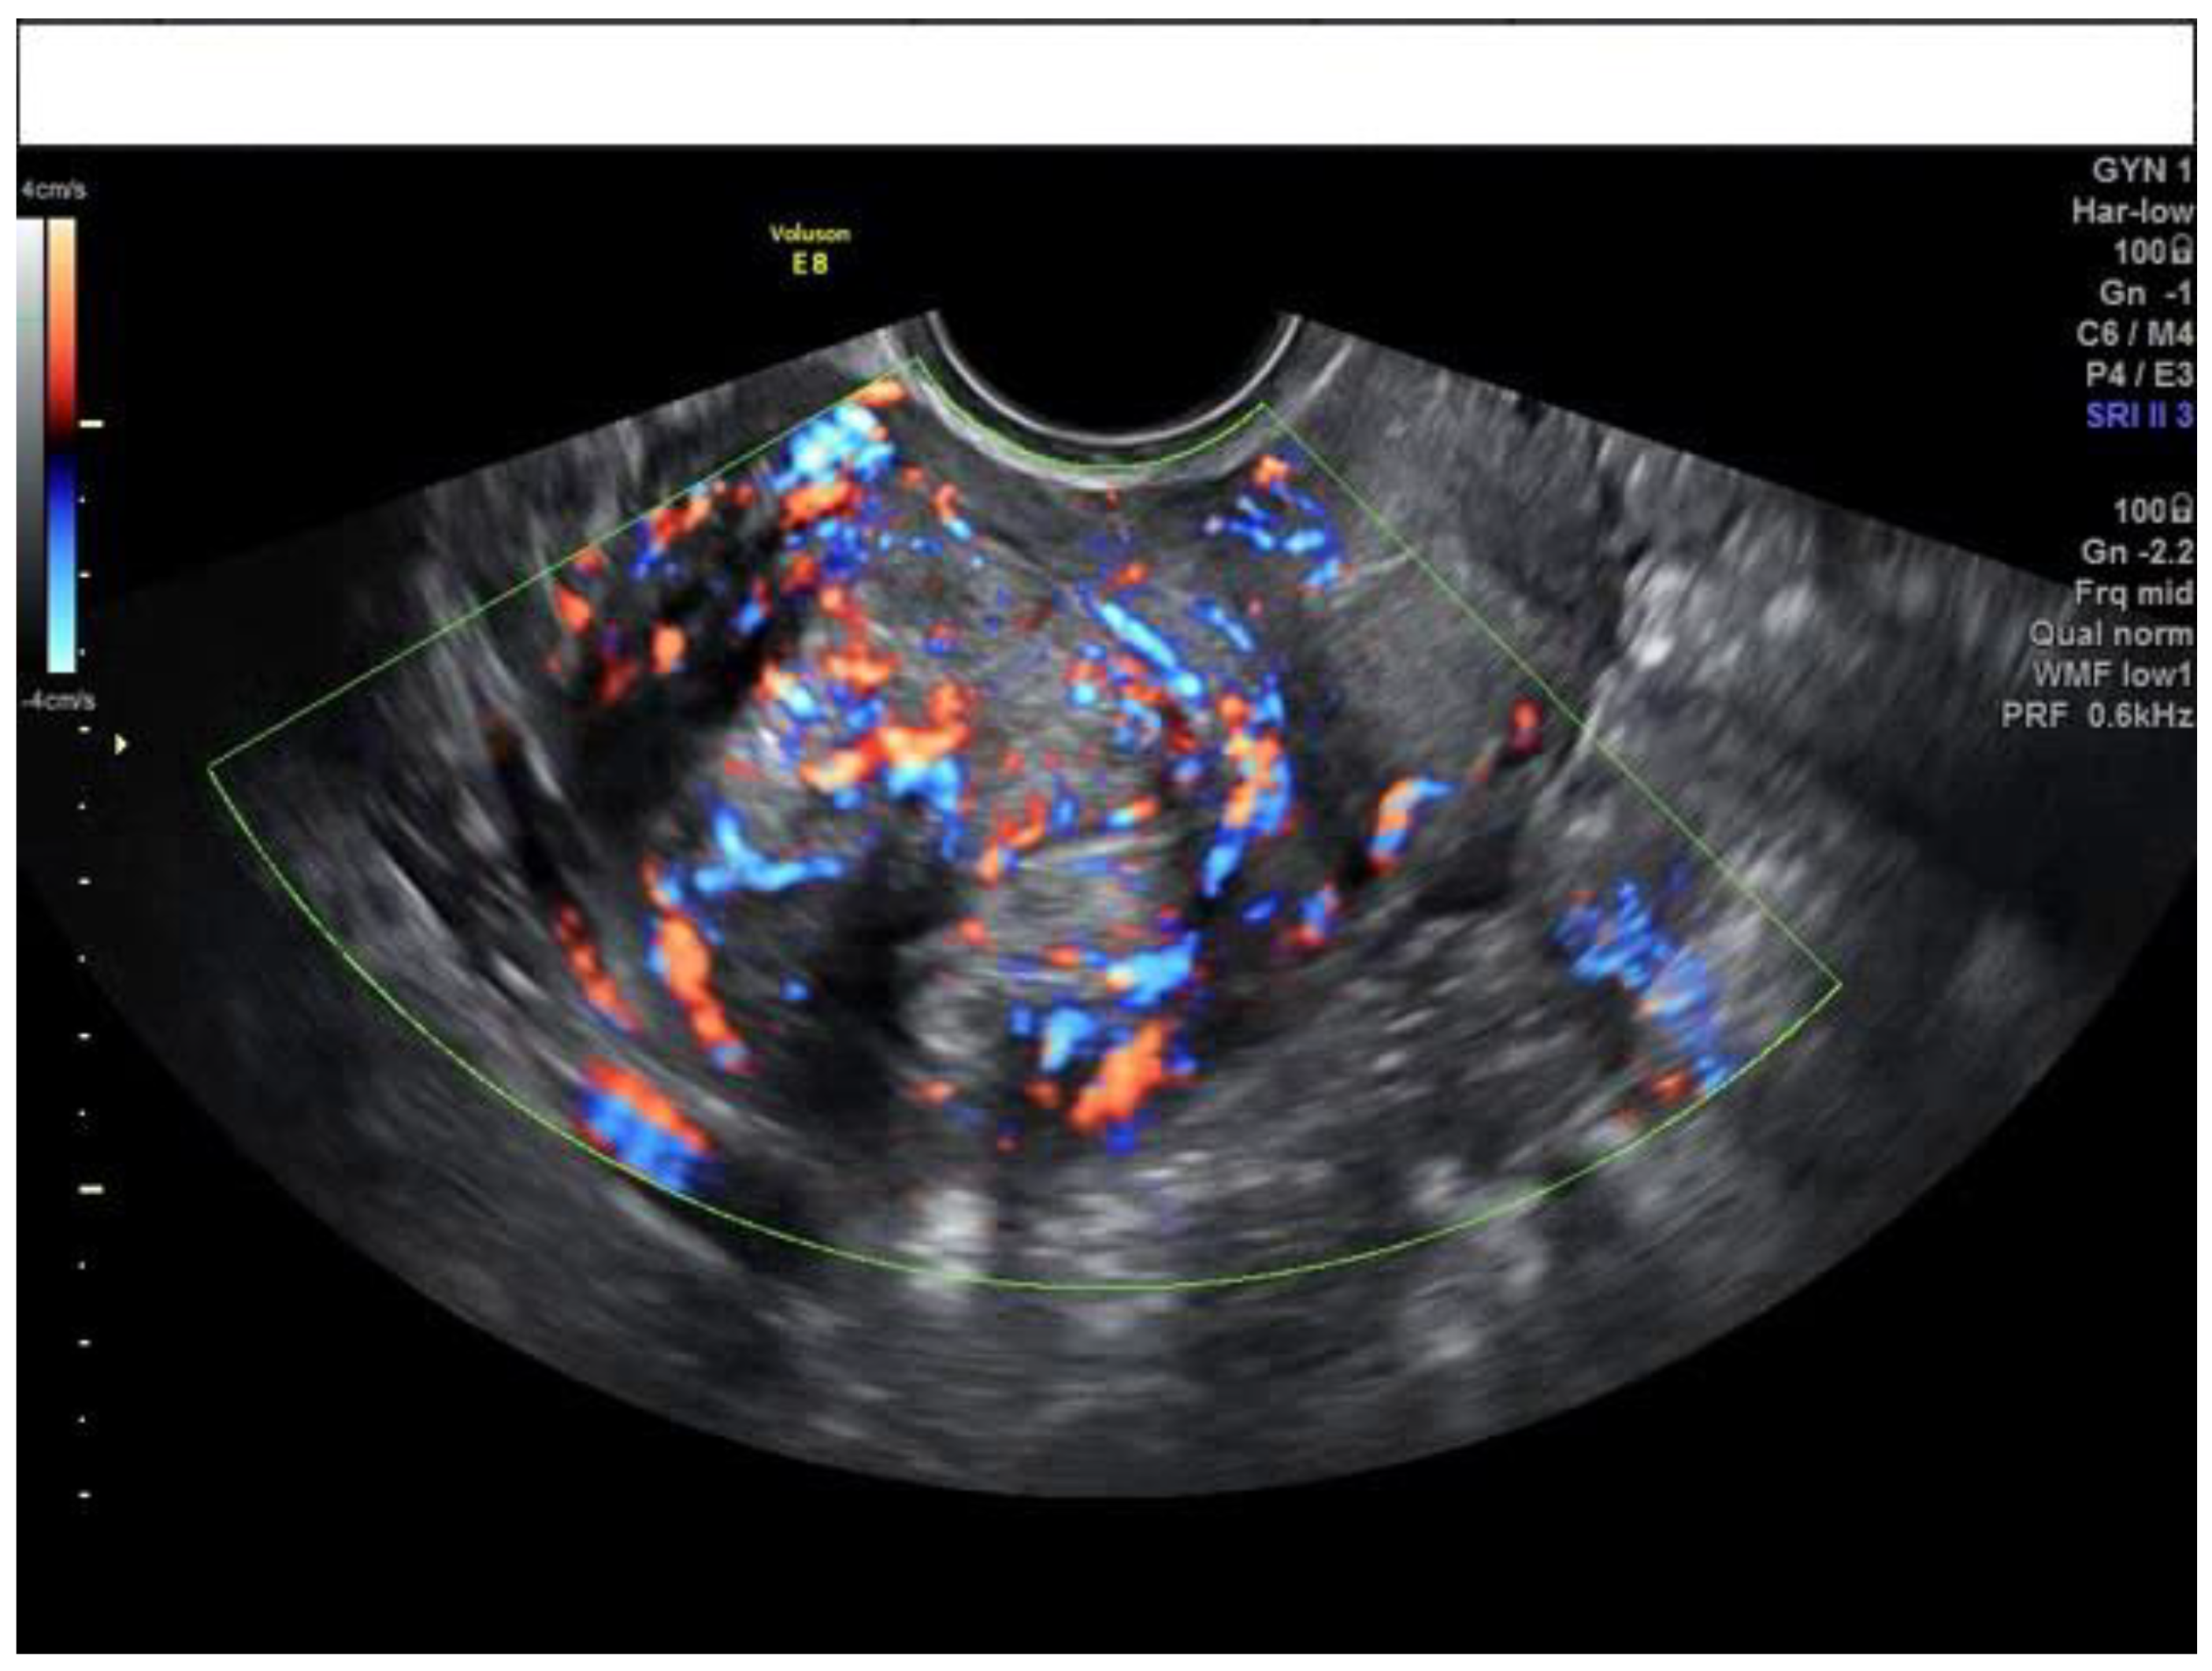

2.3. Ultrasound Assessment